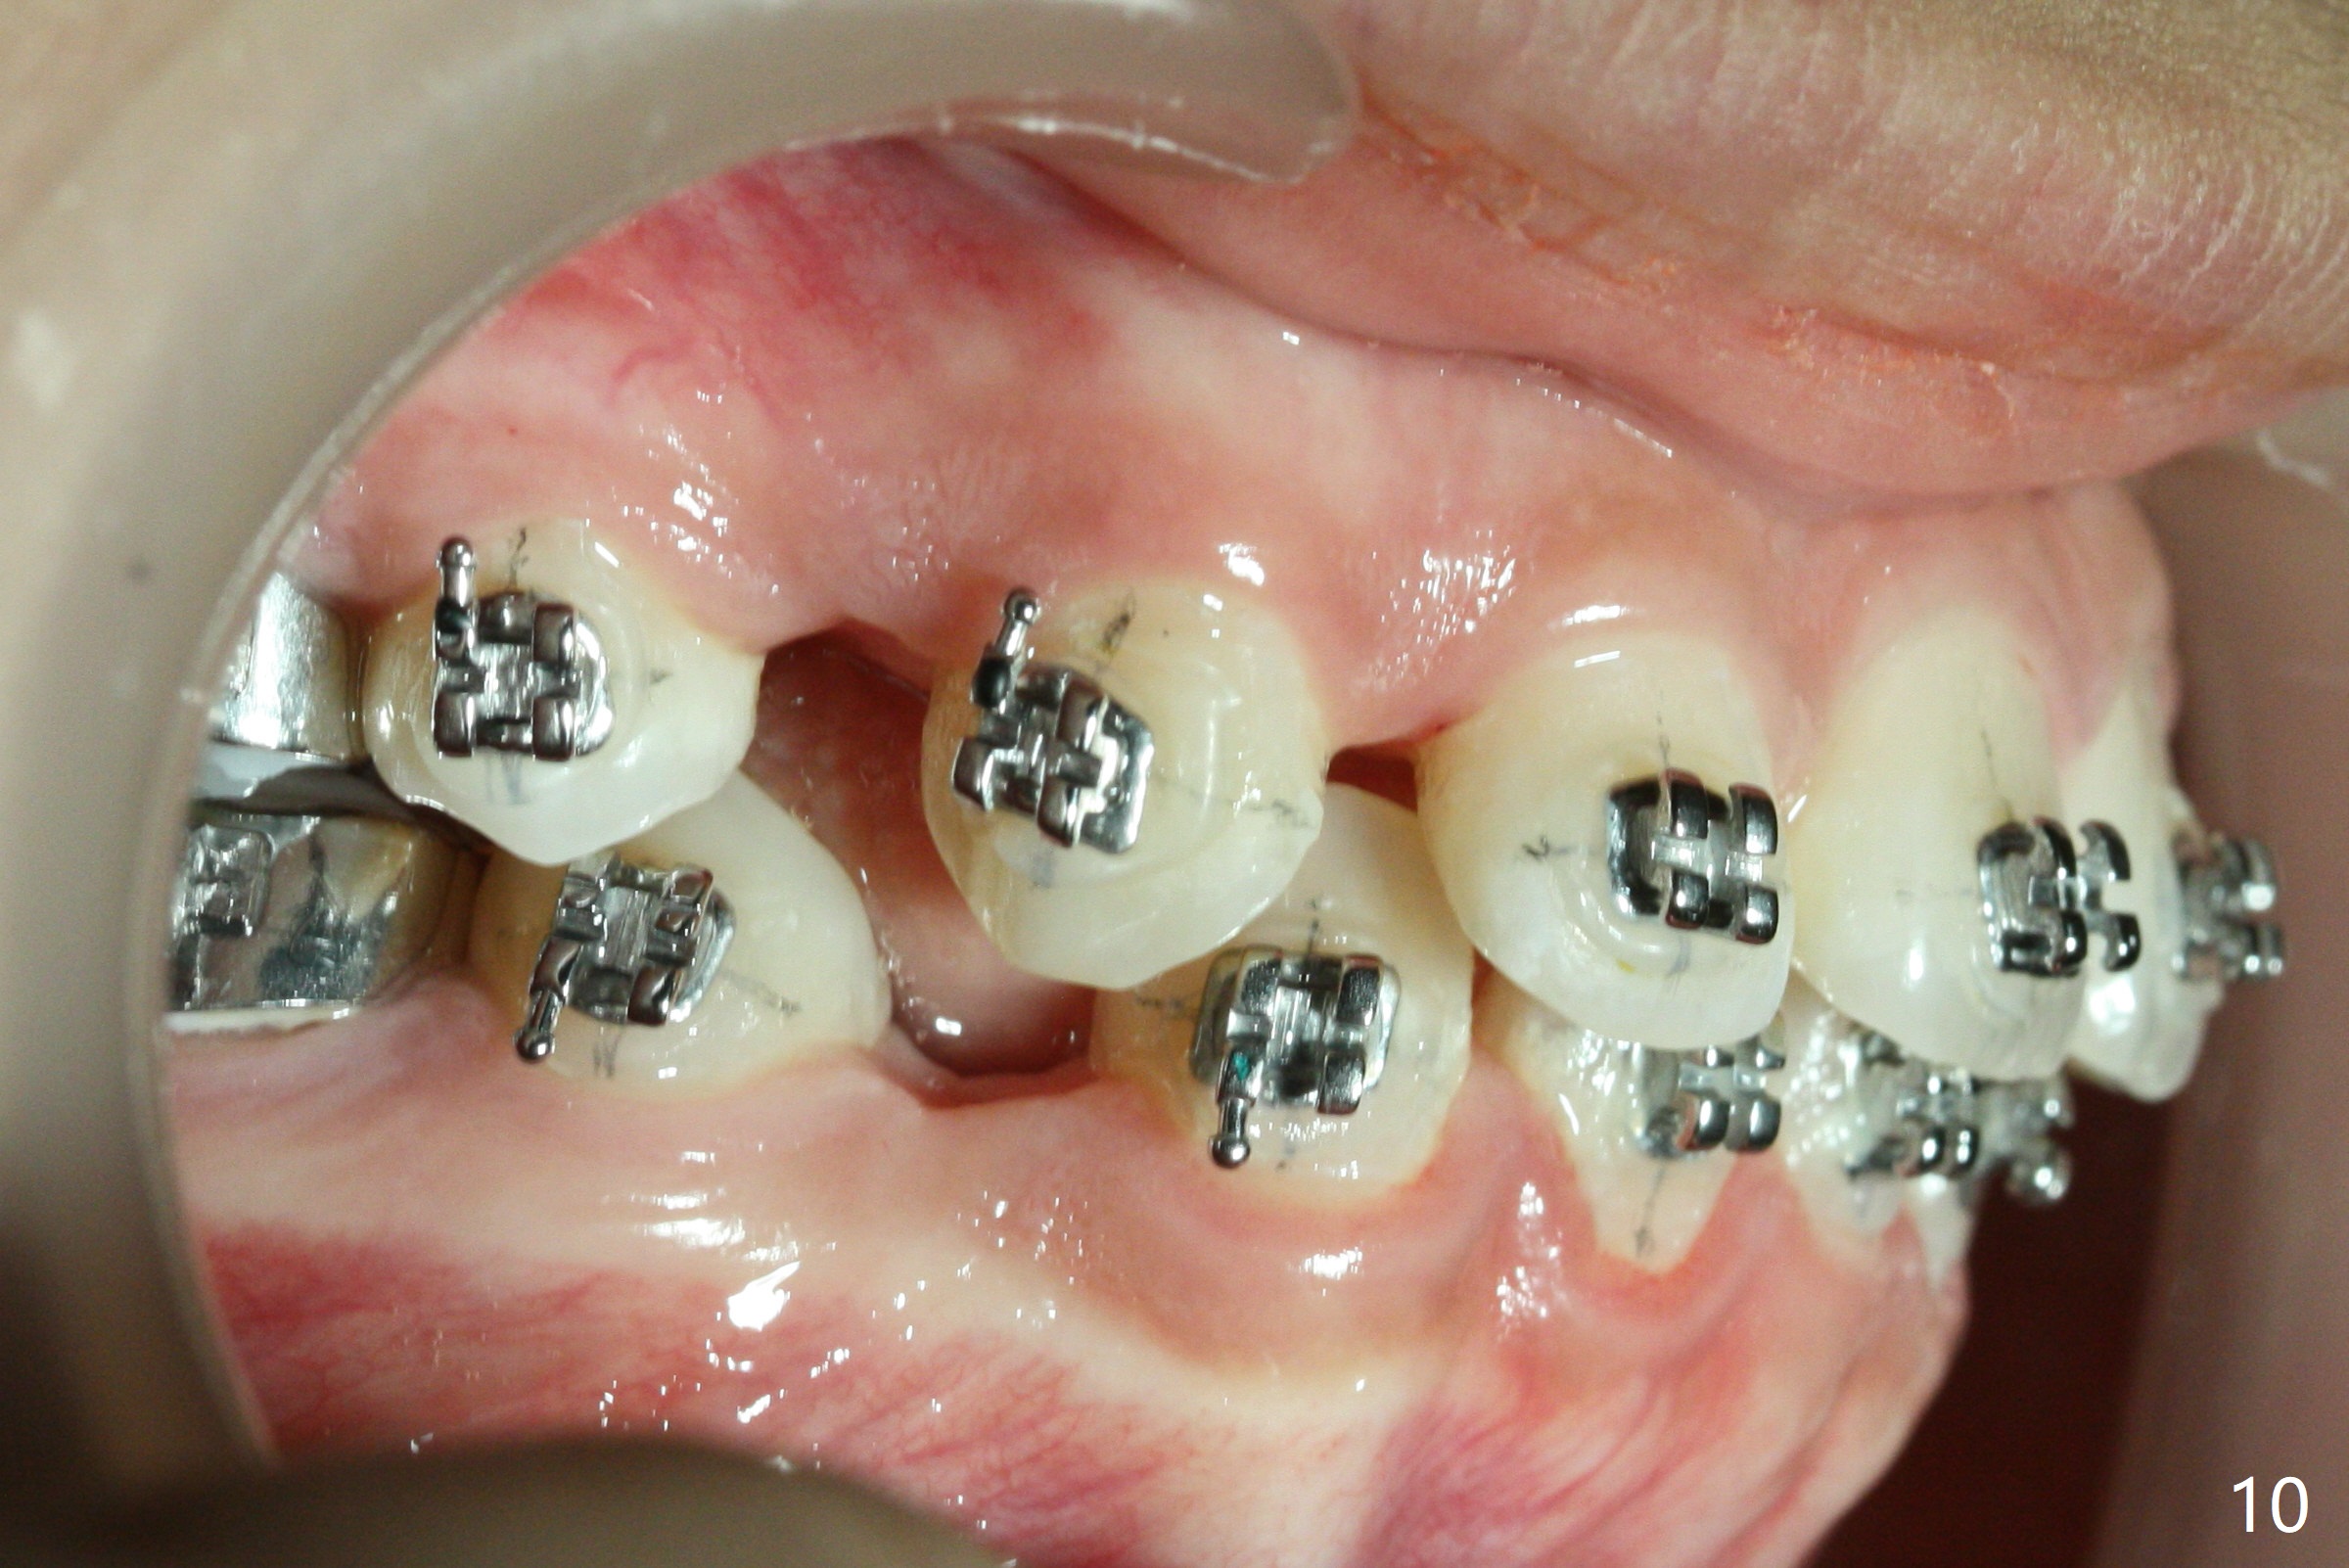

Nearly 3 months post extraction, UL 3 (Fig.7 arrow), LR 3 (Fig.8 *) and UR 3 have distalized by themselves. After changing 16 niti wires, power chains x 4 are placed between 3 and 6 (Fig.7,8) to lay foundation to reduce upper anterior overjet and lower crowding (including LL2 linguoversion). When the space between LR 2 and 3 increases (Fig. 8 *), it will be easy to shift the lower midline (Fig.5) to the right as an open coil spring will be placed between LL 1 and 3. Check the facial and dental midlines next visit before removing the wires.

Due to moving out of state, the patient returns 2.5 months post last visit (5 months post banding). No sufficient space has been created for LL2 (Fig.9), while U3s have been distalized (quicker than the lower counterparts (because of soft bone)). The upper wire is changed to 18 niti without power chains, while the lower one remains 16 niti. Ligature wire is applied to LL5 and 6 as an anchor, while power chains of two are placed between LL3 and 5. Next visit add open coil spring between LL 1 and 3 for the lower midline correction as described above.